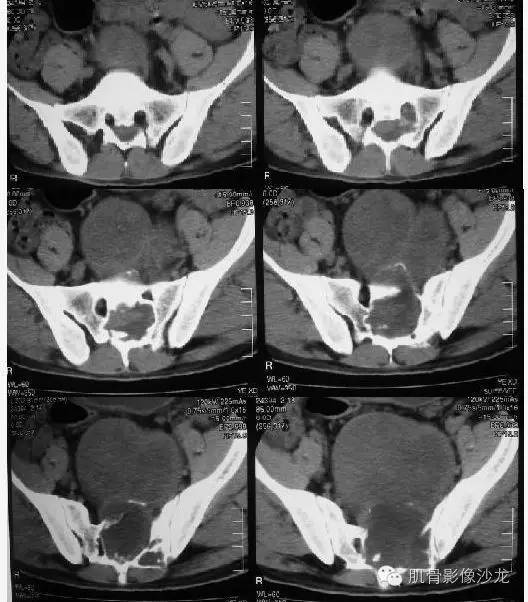

【病例】骶骨神经纤维瘤一例CT影像表现

从轴位像上看,病变起源于骶管内可能性大

从骶管向外膨胀

骶管出来的,N源可能

软组织范围大于骨质破坏,向盆腔方向生长远远大于向背侧,所以考虑软织来源

骶孔扩大,哑铃样生长,密度不均匀,强化不均匀强化

病史:32岁,男性,大小便困难2年,加重伴左侧腰骶部疼痛2个月。

病理:骶骨神经纤维瘤,细胞生长活跃伴局部细胞异型性。